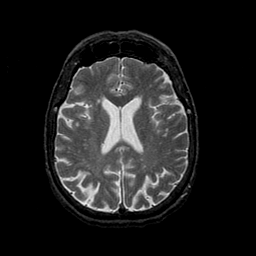

Normal aging, overlay -- Slice #33

[Home][Help][Clinical] Slice 33